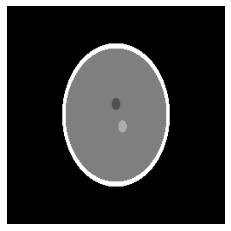

Zatem jeśli chcemy dać z=0 ujrzymy tylko przeciętą kulę, która odpowiada elipsie nr 5. Przyjrzyjmy się pierwszemu przypadkowi, czyli z=-0.25 (Rys. 4).

Rys. 4 Przekrój w punkcie z=-0.25

Jak widzimy nieco różni się on od fantomu Shepp-Logan w przestrzeni dwuwymiarowej, bo tak jak wspomniałam, nie mamy tutaj dwóch elips, które znajdą się w innym plastrze. Wykonamy teraz przekrój dla z=0, zmieniając wartość przy z_slice (Rys. 5).